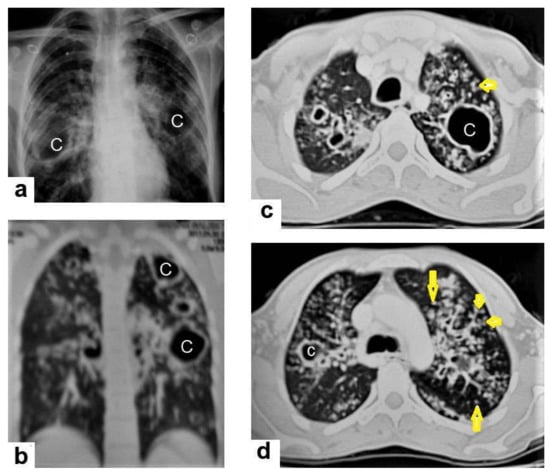

• Cavitation (Figure 3 and Figure 4) is a common finding in postprimary TB, and it is characterized as being several centimeters in size with thick irregular walls. Cavities are often seen within consolidation and may persist after treatment predisposing to a bacterial or fungal superinfection or adjacent vascular erosion causing hemoptysis [1,10]. In postprimary TB, both consolidation and cavitation have a predilection for the apical and posterior segments of the upper lobes and the upper segments of the lower lobes [1,14]. This predilection of TB is attributed to the relative over-ventilation, high oxygen tension, and delayed lymphatic clearance in these regions [16]. Thick wall cavities are an important differential diagnosis of a pulmonary abscess, septic emboli, aspergilloma, granulomatosis with polyangitis (Wegener’s granulomatosis), lung malignancy, and others [17].

• Centrilobular nodules (Figure 4 and Figure 5) occur due to the communication of active TB with the bronchial tree resulting in endobronchial spread. It occurs in most cases of active TB. It appears as centrilobular nodules and a tree-in-bud sign on CT images [1,10]. The tree-in-bud pattern is seen on high-resolution CT images as 2–4 mm centrilobular nodules of soft tissue density that are connected to multiple branching linear structures of the similar caliber, arising from a single stalk. It commonly occurs in the endobronchial spread of TB and is highly suggestive of active TB. However, a tree-in-bud is a CT manifestation of the diverse entities of lung diseases, including TB, cytomegalovirus, respiratory syncytial virus, obliterative bronchiolitis, diffuse panbronchiolitis, cystic fibrosis, airway-invasive aspergillosis, allergic bronchopulmonary aspergillosis, and pulmonary metastasis [18].

Figure 3. Post primary TB in a 45-year-old male with cough and hemoptysis. Axial images of chest CT show (a) cavitary lesions in the right upper lobe and upper segment of the left lower lobe surrounded with consolidation, (b) cavitary lesion in the upper segment of the left lower lobe with thick irregular wall surrounded by patchy ground glass opacities, (c) centrilobular nodules and tree-in-bud nodules, and (d) consolidation in the left lower lobe with air-bronchograms.